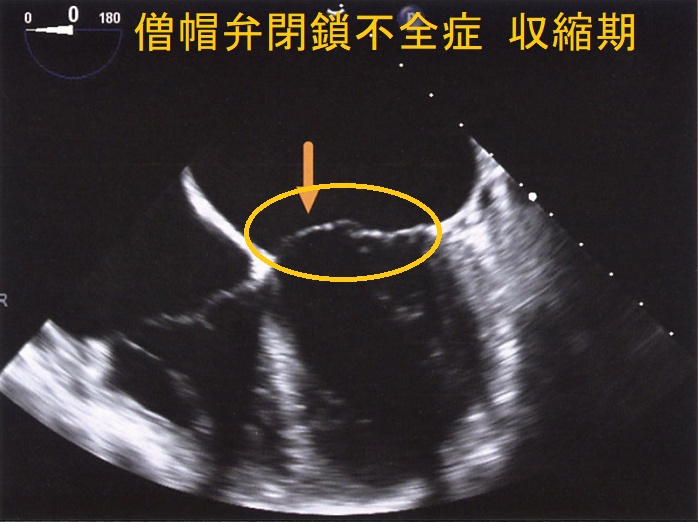

僧帽弁閉鎖不全症(MR)は、

- 僧帽弁破壊:動脈硬化、リウマチ熱による僧帽弁の石灰化、感染性心内膜炎

- 僧帽弁逸脱:閉塞性肥大型心筋症、甲状腺機能亢進症の30%に起こる

- 乳頭筋障害・心筋障害:

①拡張型心筋症(DCM)

②虚血性心疾患(狭心症/心筋梗塞)

心筋梗塞(右冠状動脈、回旋枝梗塞)による乳頭筋断裂→急性の僧帽弁閉鎖不全(MR)と急性左心不全

虚血性心疾患(狭心症/心筋梗塞)では腱索/乳頭筋が断裂しなくても、左室・左房・僧帽弁輪拡大、壁運動低下により僧帽弁閉鎖不全症(MR)

甲状腺機能亢進症/バセドウ病、甲状腺機能低下症/橋本病(下記)

などが原因となります。

甲状腺機能亢進症/バセドウ病、甲状腺機能低下症/橋本病では僧帽弁腱索/乳頭筋断裂の頻度が高い(Endocr Rev. 2005;26(5):704–728.)。

自己免疫性に粘液多糖類が蓄積し、僧帽弁の粘液水腫性変化が生じます

- 甲状腺機能亢進症/バセドウ病の33%

- 甲状腺機能低下症/橋本病の36%

(Thyroid. 2002 Mar; 12(3):193-5.)

特に循環血液量・心拍出量が増加する甲状腺機能亢進症/バセドウ病では、僧帽弁腱索/乳頭筋断裂を引きおこす危険性が高い。(J Endocr Soc. 2018 Sep 17;2(11):1246-1250.)[Endocrinol Diabetes Metab Case Rep. 2022 Jul 1;2022:22-0298.]

僧帽弁腱索/乳頭筋断裂がなく、粘液腫性変性による中等度から重度の僧帽弁閉鎖不全症(MR)なら、甲状腺機能の正常化に伴い改善する可能性があります。[BMJ Case Rep. 2021 Feb 4;14(2):e239626.]